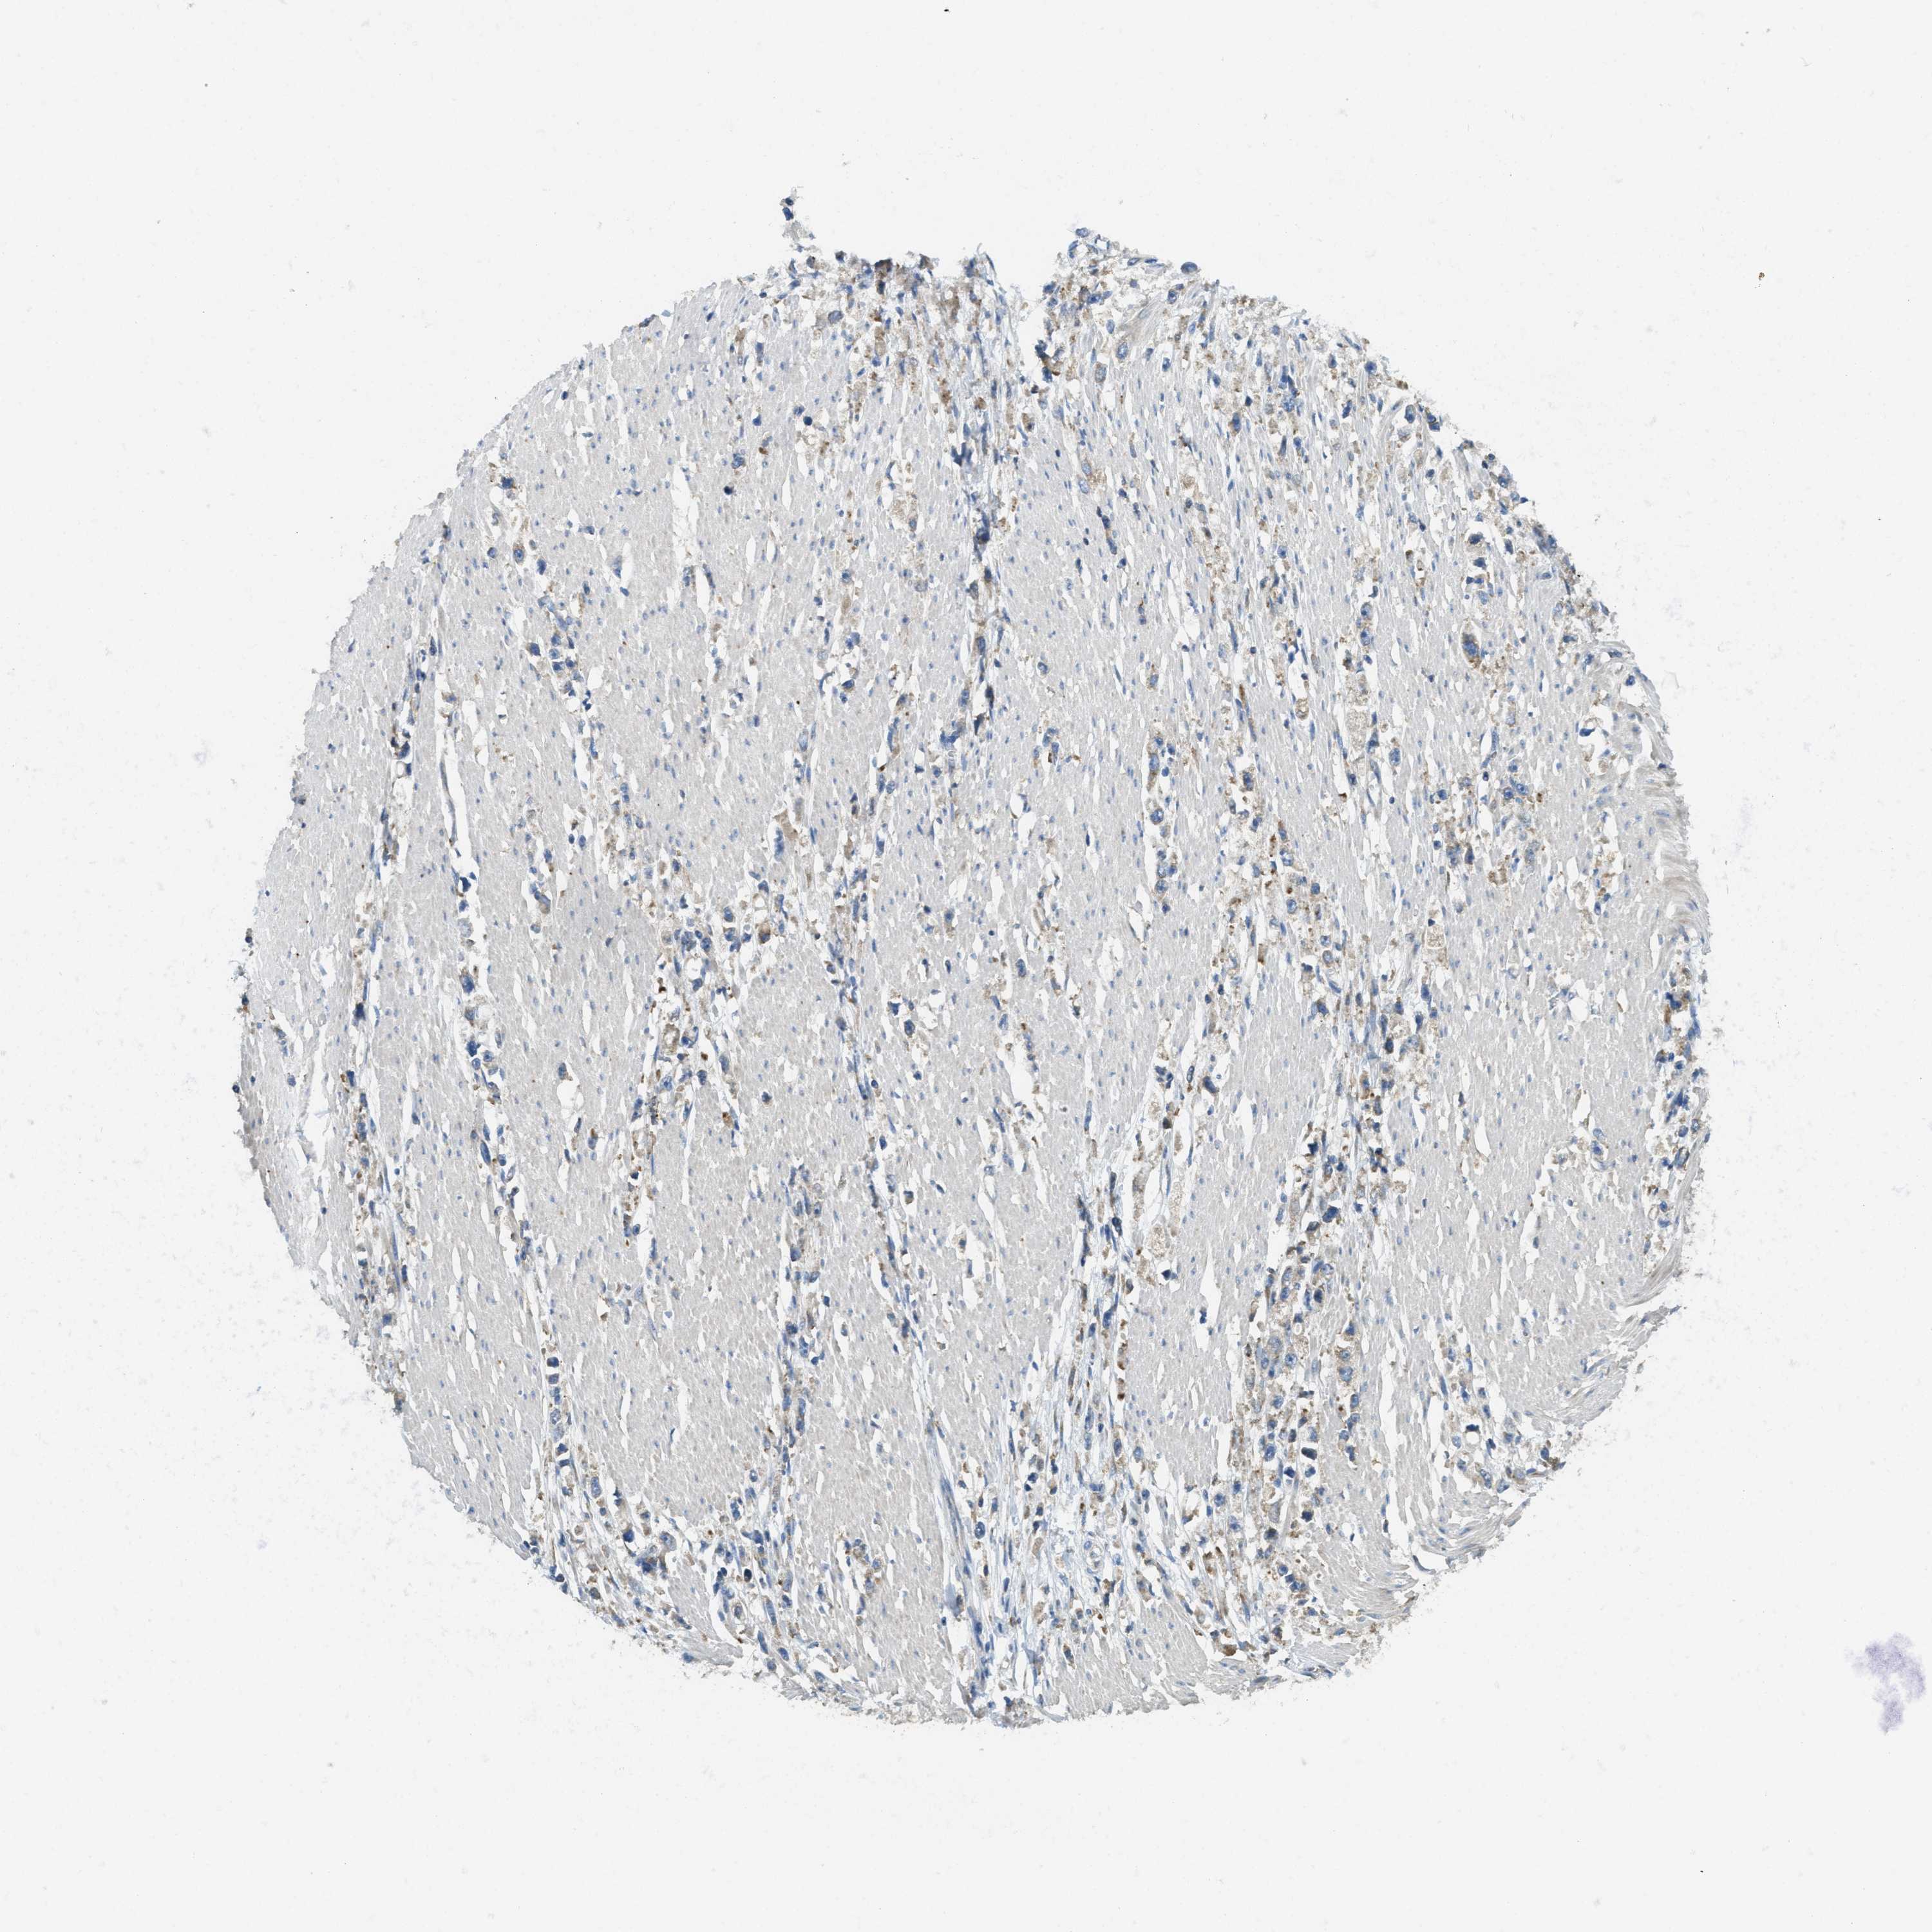

STOMACH CANCER - Protein expressioni

A mouse-over function shows sample information and annotation data. Click on an image to view it in a full screen mode. Samples can be filtered based on level of antibody staining by selecting one or several of the following categories: high, medium, low and not detected. The assay and annotation is described here.

Note that samples used for immunohistochemistry by the Human Protein Atlas do not correspond to samples in the TCGA dataset.

Antibody stainingi

Antibody staining in the annotated cell types in the current human tissue is reported as not detected, low, medium, or high, based on conventional immunohistochemistry profiling in selected tissues. This score is based on the combination of the staining intensity and fraction of stained cells.

Each image is clickable and will lead to virtual microscopy that enables deeper exploration of all samples and also displays staining intensity scores, fraction scores and subcellular localization as well as patient and tissue information for each sample.

Antibody HPA011276

Antibody HPA017062

Staining

High

Medium

Low

Not detected

Intensity

Strong

Moderate

Weak

Negative

Quantity

>75%

75%-25%

<25%

None

Location

Nuclear

Cytoplasmic/membranous

Cytoplasmic/membranous,nuclear

Adenocarcinoma, NOS

Adenocarcinoma, High grade